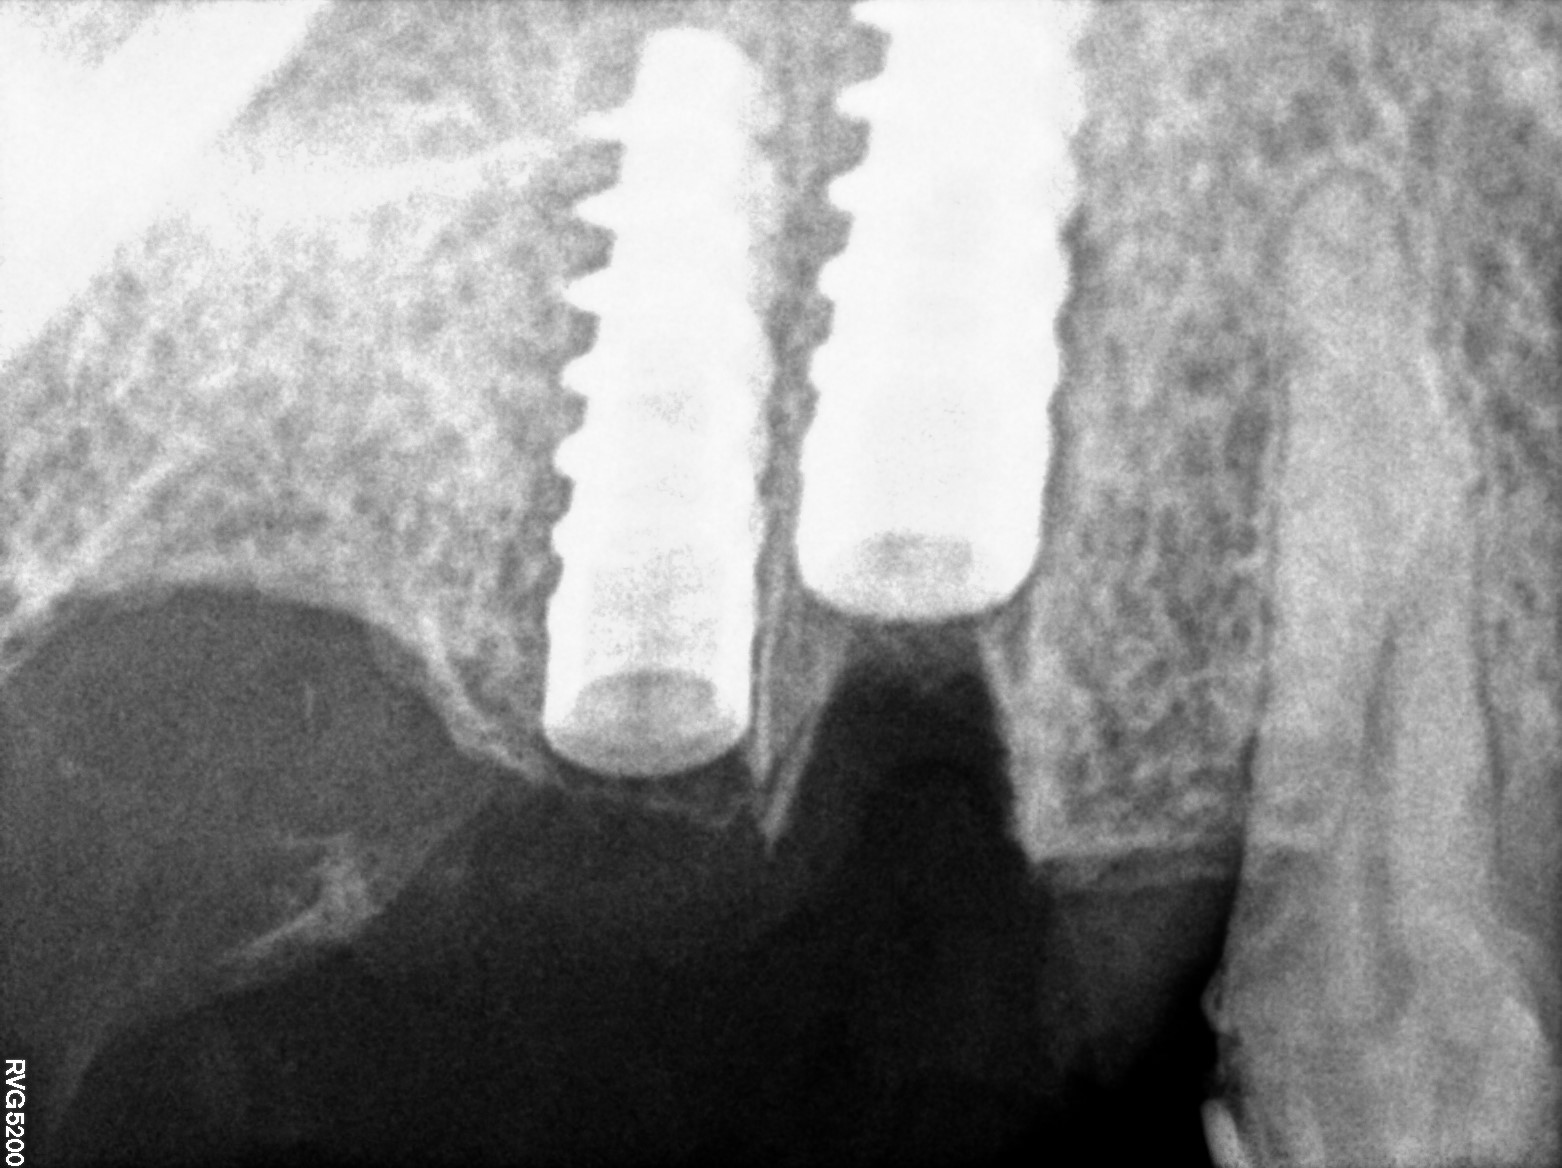

Dental Radiographs FHIR: DocumentReference · LOINC 24641-7

R66.jpg

24641-7